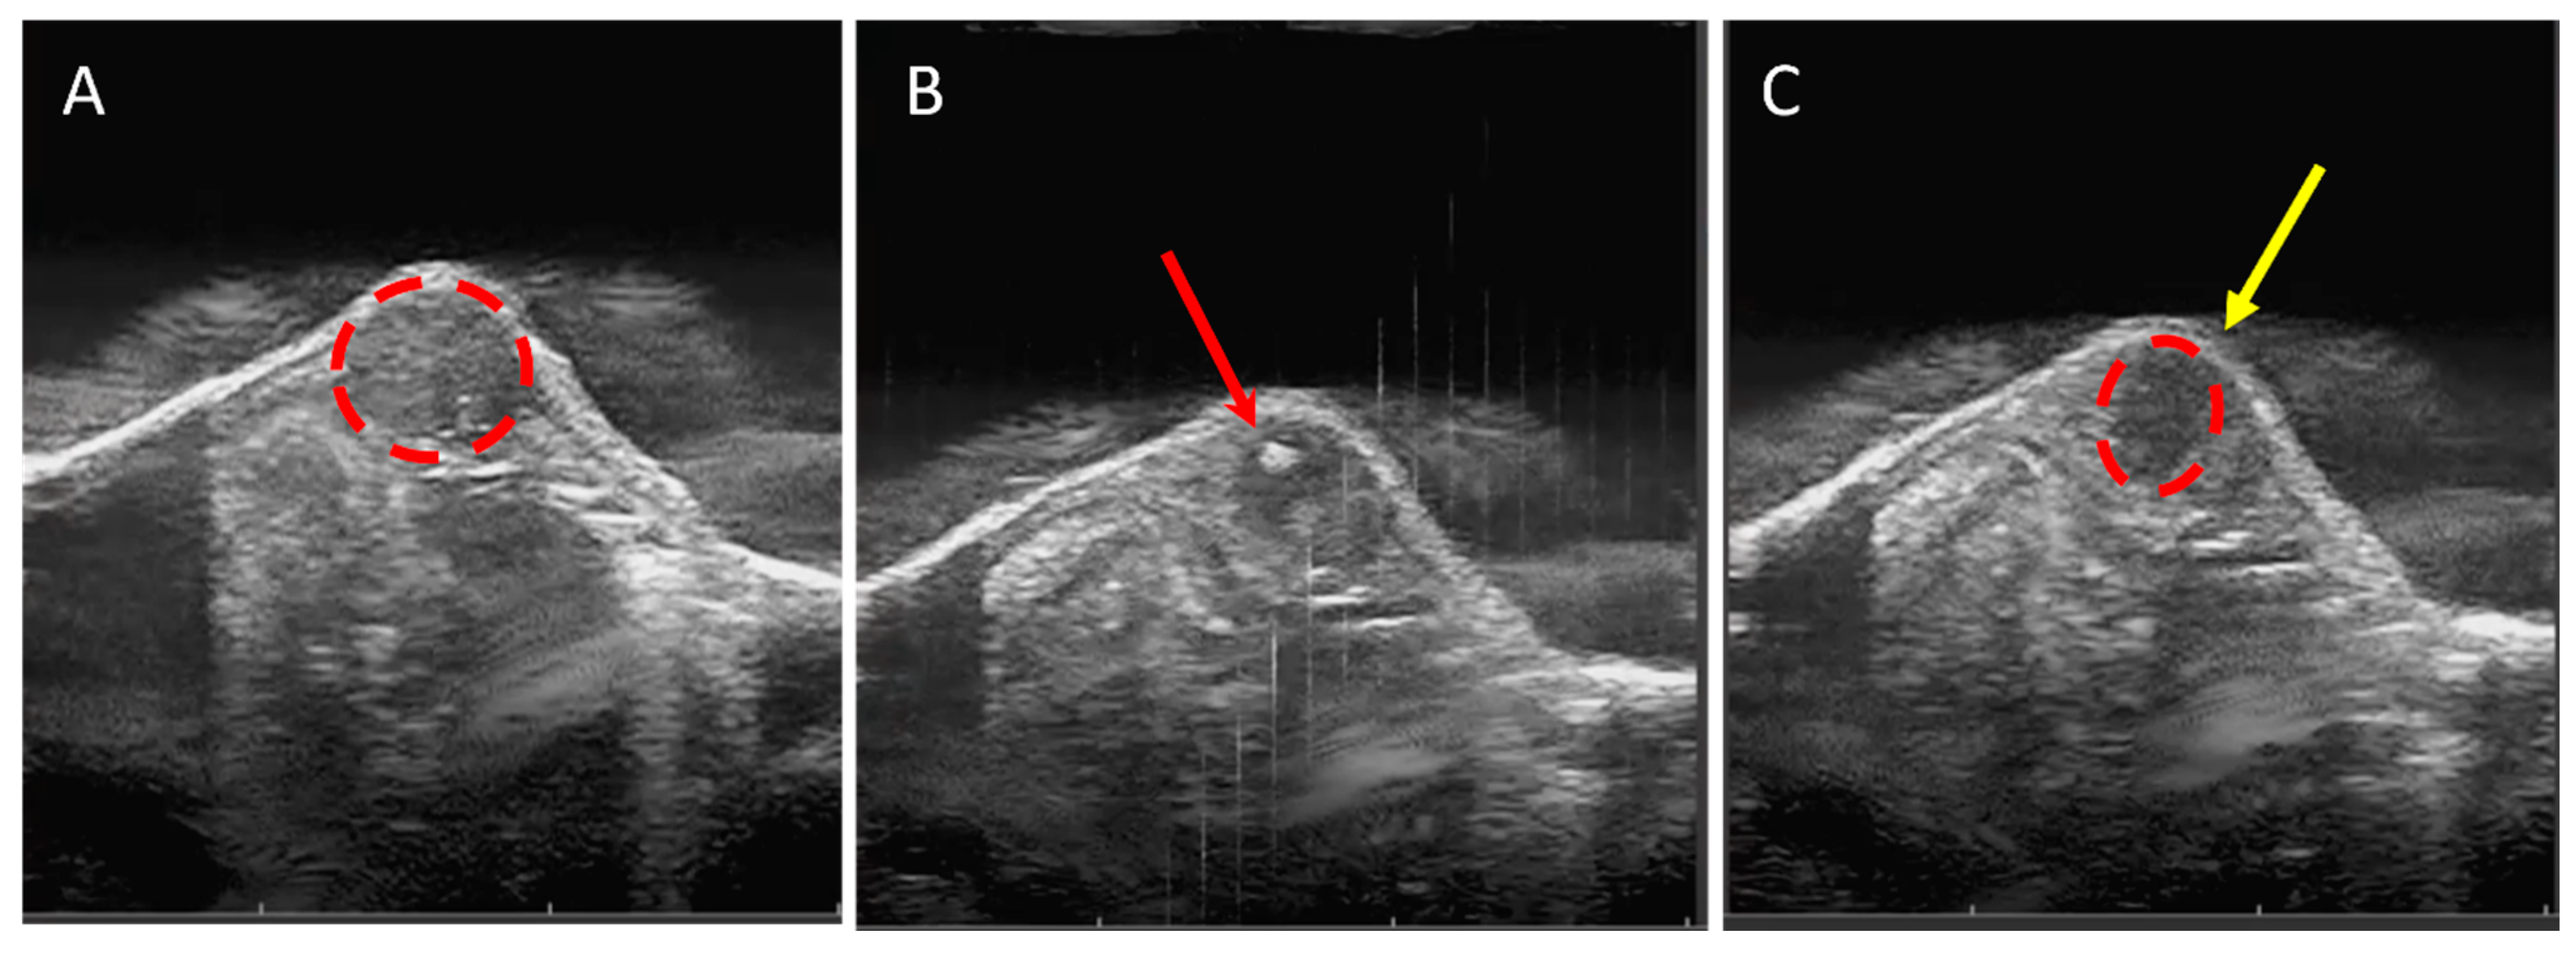

3.1. Tumor Tissue Can Be Effectively and Precisely Targeted and Ablated with Histotripsy